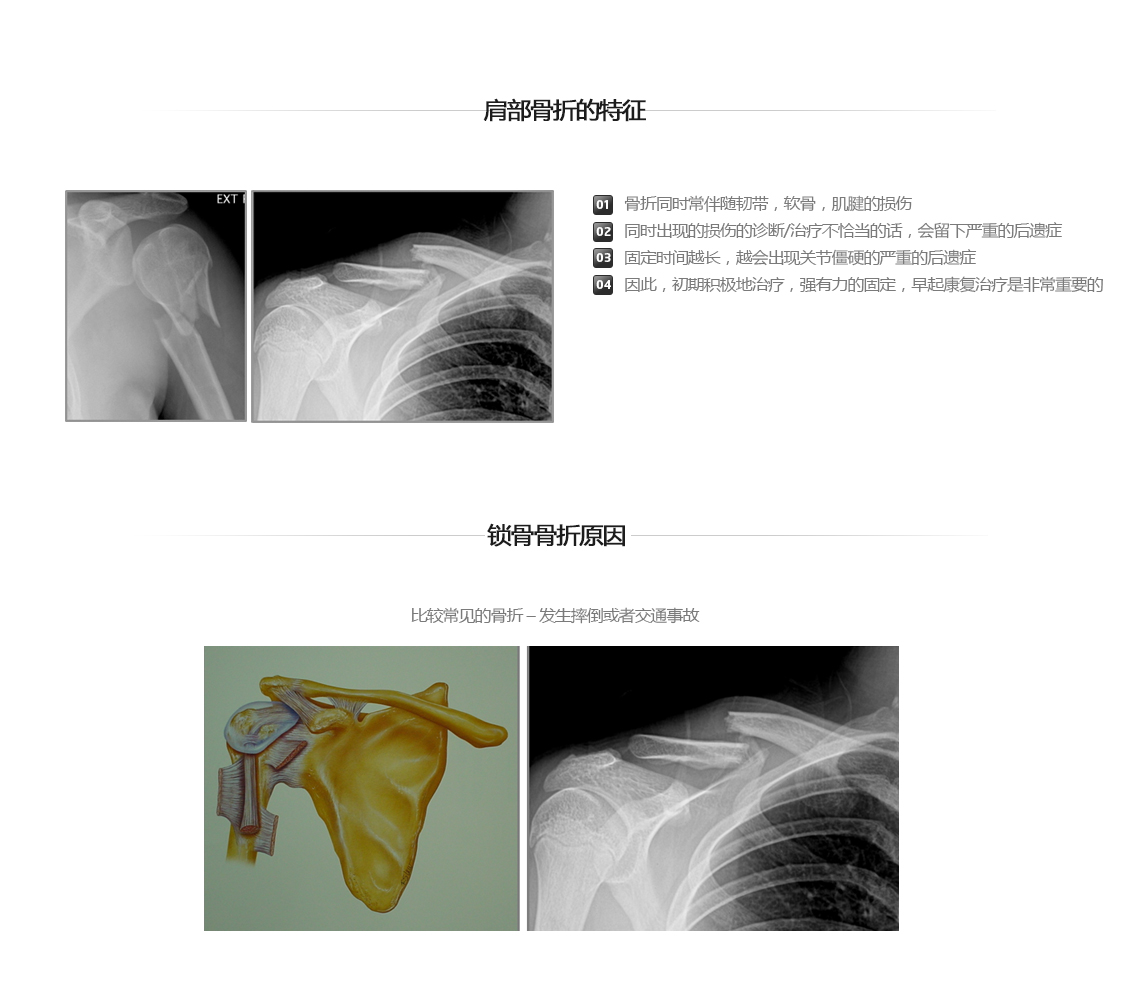

肩部关节骨折